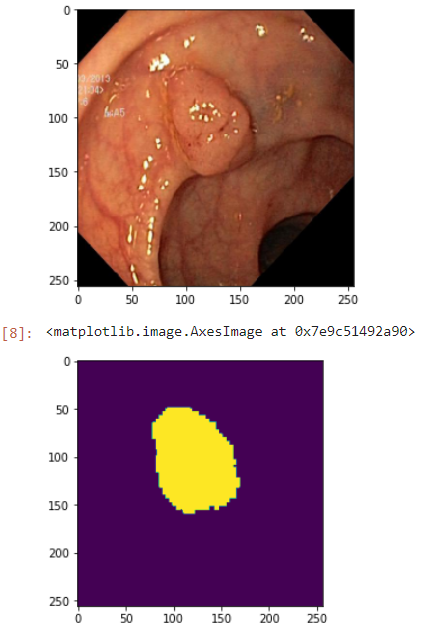

今天,我们将使用 U-Net 架构对 Kvasir 数据集中的图像进行分割。该数据集是在挪威 Vestre Viken 健康基金会(VV)使用内窥镜设备收集的。数据集已被经验丰富的内窥镜医生标记。您可以在此处访问数据集。我们首先导入所需的库。

这个脚本从给定目录(images_path)获取图像文件。然后它将每张图像调整到给定的大小(256x256 像素)并保存在 numpy 数组(X)中。掩码也执行相同的过程。掩码也被调整到相同的大小并保存在 numpy 数组(y)中。结果,数组 X 包含处理后的图像,而数组 y 包含处理后的掩码。让我们看一个示例图像及其掩码:

让我们看看我们的结果: